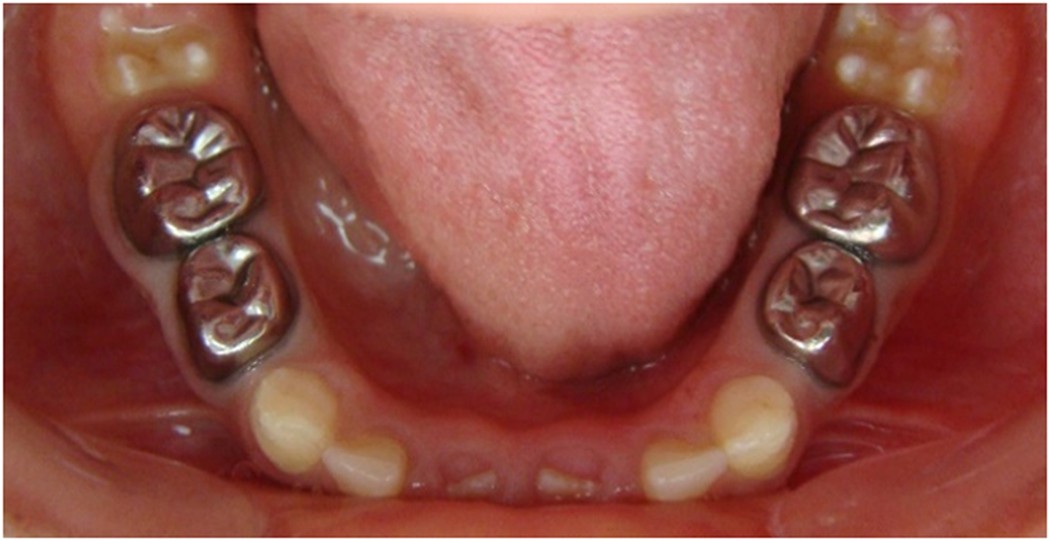

Figure 7

Six months after treatment.